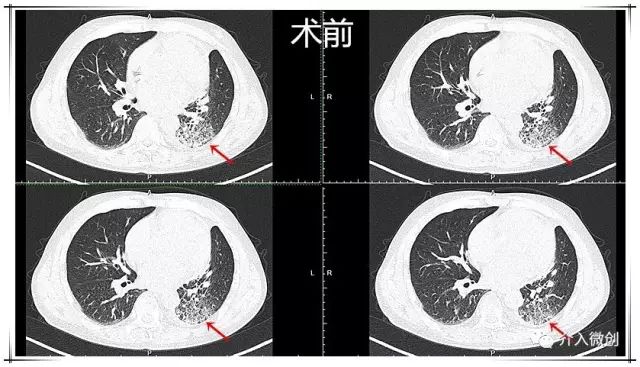

例2:左肺小细胞肺癌放化疗后进展

中年男性患者,左肺小细胞肺癌(局限期),经过EP方案化疗7周期,期间配合同步左肺及纵隔病灶外放疗。治疗后期左下肺病灶持续进展,经调整化疗剂量仍反复出现严重不良反应,无法耐受进一步静脉化疗。

患者顺利完成2周期动脉灌注化疗,耐受性良好,无明显化疗毒副反应。术后1月后复查CT示左下肺病灶基本消失,术后随访3年余病情一直持续稳定,疗效评价完全缓解。